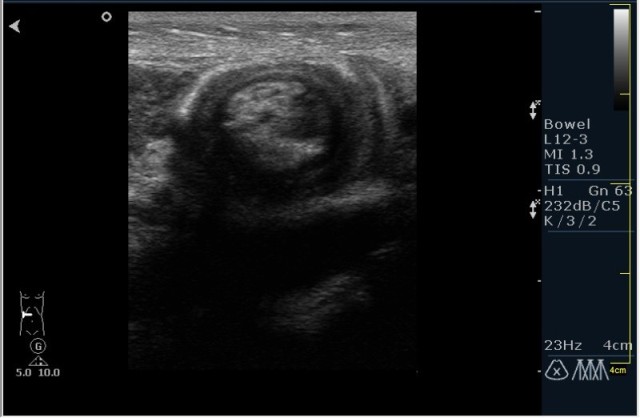

Ребёнок с болями в животе.

инвагинация! :!:

На представленных сонограммах определяется типичная "мишень" или "кокарда" (7ая и 8ая сонограмма сверху), которая при продольном сканировании превращается в "телескоп" (сонограммы 3 & 4). Все это указывет на инвагинацию кишечника (илео-цекальную). Причиной явилось лимфаденопатия брыжейки (которую вы указали). Увеличеные лимфоузлы вместе с инвагинатом хорошо различимы в просвете толстой кишки.

Уважаемые коллеги! Без сомнения имеет место илео-цекальная инвагинация.увеличенные овальные лимфоузлы, да еще такими гроздями характерны для мезаденита.Все зависит от развертывания клинической симптоматики.

Вариант 1- развите острого мезаденита спровоцировало инвагинацию.

вариант 2 - повторяющиеся эпизоды инвагинации привели к лимфоаденопатии.